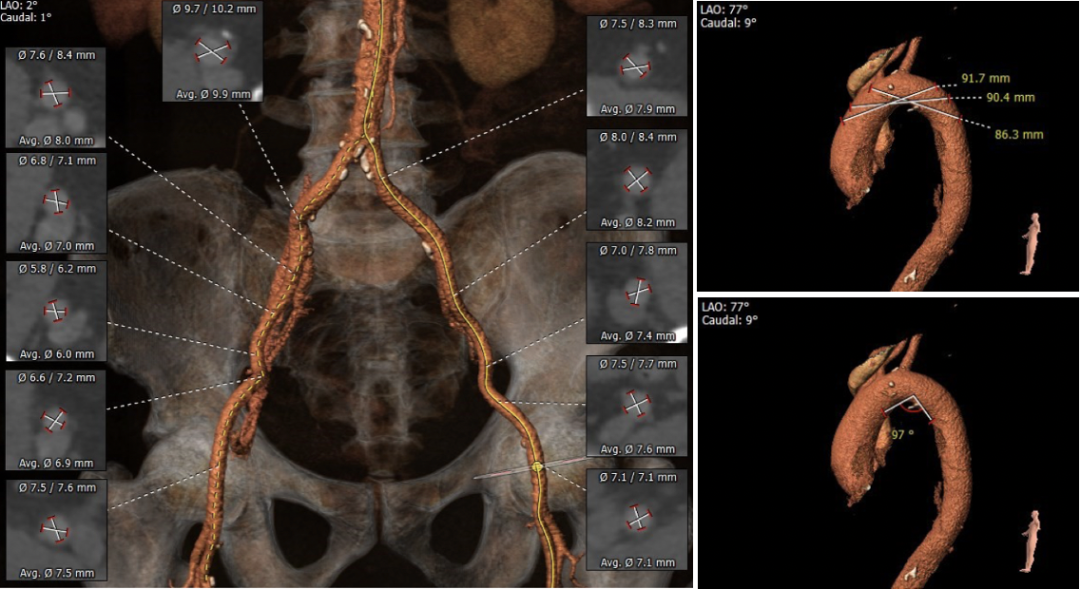

主动脉根部测量

冠脉高度及瓣叶长度测量

钙化分布

瓣环上多平面测量

外周血管及主动脉弓解剖

右冠高度合适,左冠高度稍低,左冠瓣长度>冠脉开口与瓣叶附着缘距离。

主动脉瓣环与水平面夹角稍大,双侧血管整体入路条件良好。